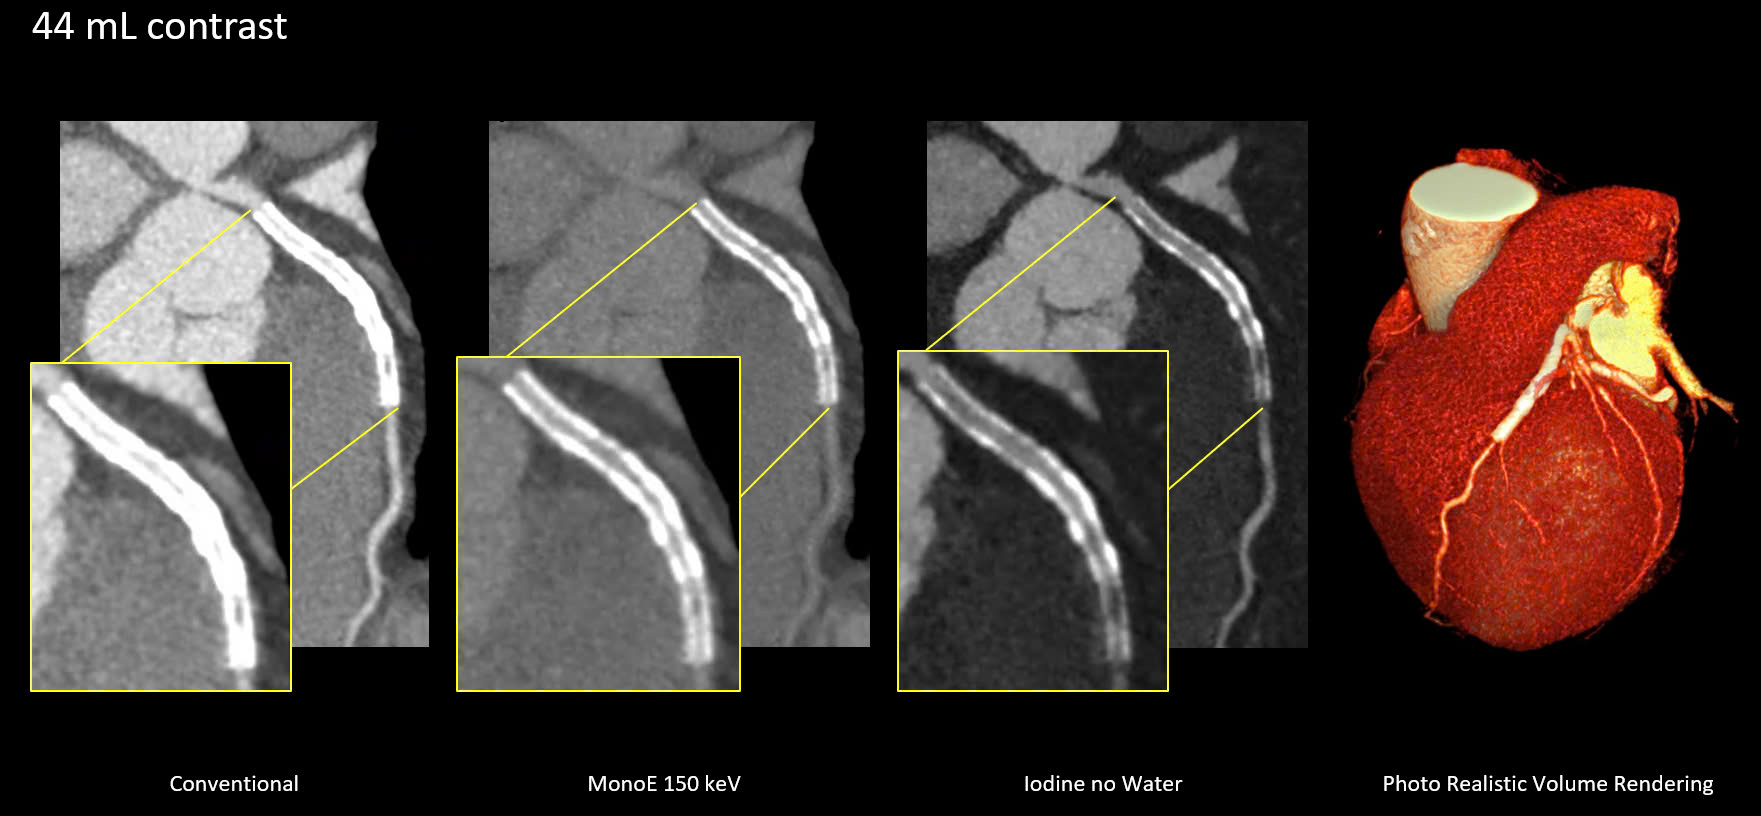

Bệnh nhân được chỉ định thay van động mạch chủ qua da. Các bác sĩ đã sử dụng chương trình TAVI planning trên hệ thống Spectral CT7500 với liều lượng thuốc cản quang giảm, nhờ tính năng phổ MonoE cho phép đảm bảo hình ảnh có độ tương phản cao dù bệnh nhân có nền bệnh phức tạp.

Ảnh chụp CT phổ tích hợp trí tuệ nhân tạo AI.